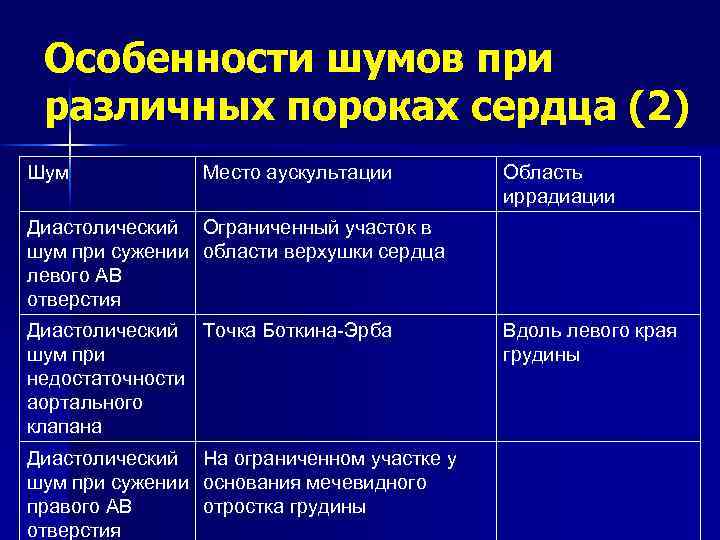

Особенности шумов при различных пороках сердца (2) Шум Место аускультации Область иррадиации Диастолический Ограниченный участок в шум при сужении области верхушки сердца левого АВ отверстия Диастолический Точка Боткина-Эрба шум при недостаточности аортального клапана Диастолический На ограниченном участке у шум при сужении основания мечевидного правого АВ отростка грудины отверстия Вдоль левого края грудины